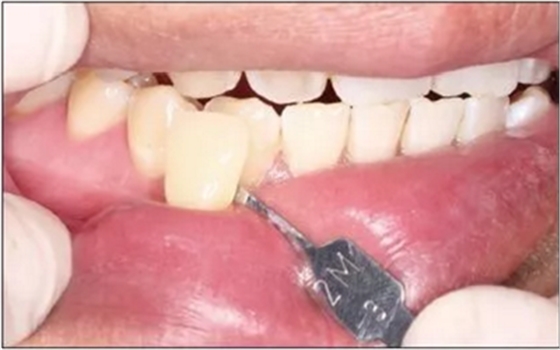

2)比色。使用VITA 3D-MASTER比色板進(jìn)行比色(圖9),比色結(jié)果為2M3。